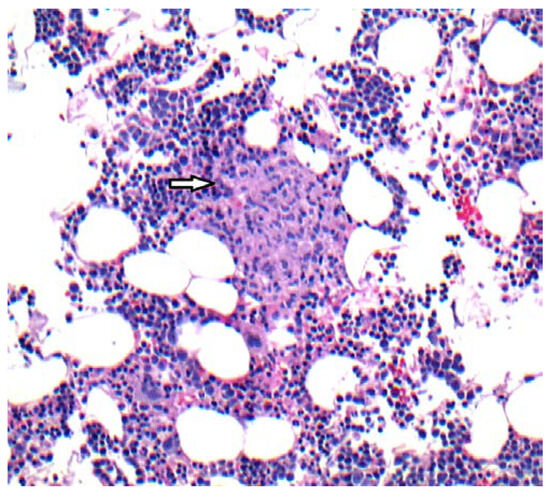

Hemophagocytic Lymphohistiocytosis (HLH): Elusive Diagnosis of Disseminated Mycobacterium avium Complex Infection

by Eloy E. Ordaya, Sulieman Abu Jarir, Robert Yoo and Pranatharthi H. Chandrasekar

Introduction: Hemophagocytic lymphohistiocytosis (HLH) is a clinical syndrome of hyperinflammation leading to an uncontrolled and ineffective immune response, associated with high mortality. Case report: A 26-year-old woman with acute lymphoblastic leukemia, 8 months in remission, was found to have HLH. Without any improvement, [...] Read more.

Introduction: Hemophagocytic lymphohistiocytosis (HLH) is a clinical syndrome of hyperinflammation leading to an uncontrolled and ineffective immune response, associated with high mortality. Case report: A 26-year-old woman with acute lymphoblastic leukemia, 8 months in remission, was found to have HLH. Without any improvement, stem cell transplantation was considered. Then, Mycobacterium avium complex (MAC) infection was identified as cause of her HLH. With appropriate therapy for infection, HLH improved and transplantation was averted. Conclusion: MAC should be included in the list of potential causes of HLH. Full article